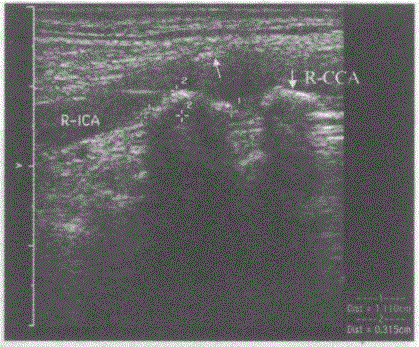

问题 临床资料:男,78岁,自述头晕1月余,体位变化站立时明显。 超声综合描述:双侧颈总、颈内动脉内膜粗糙,连续性差,中内膜增厚,管壁可见多个大小不等强回声光团,最大1.1cm×0.3cm,位于右颈总动脉分叉处,后伴声影,该段残余管腔内径0.36cm。 超声提示:

选项 A.颈动脉正常声像图 B.双侧颈动脉粥样硬化 C.双侧颈动脉粥样硬化并软斑形成 D.双侧颈动脉粥样硬化伴钙化斑形成右颈总动脉节段性狭窄

答案 D